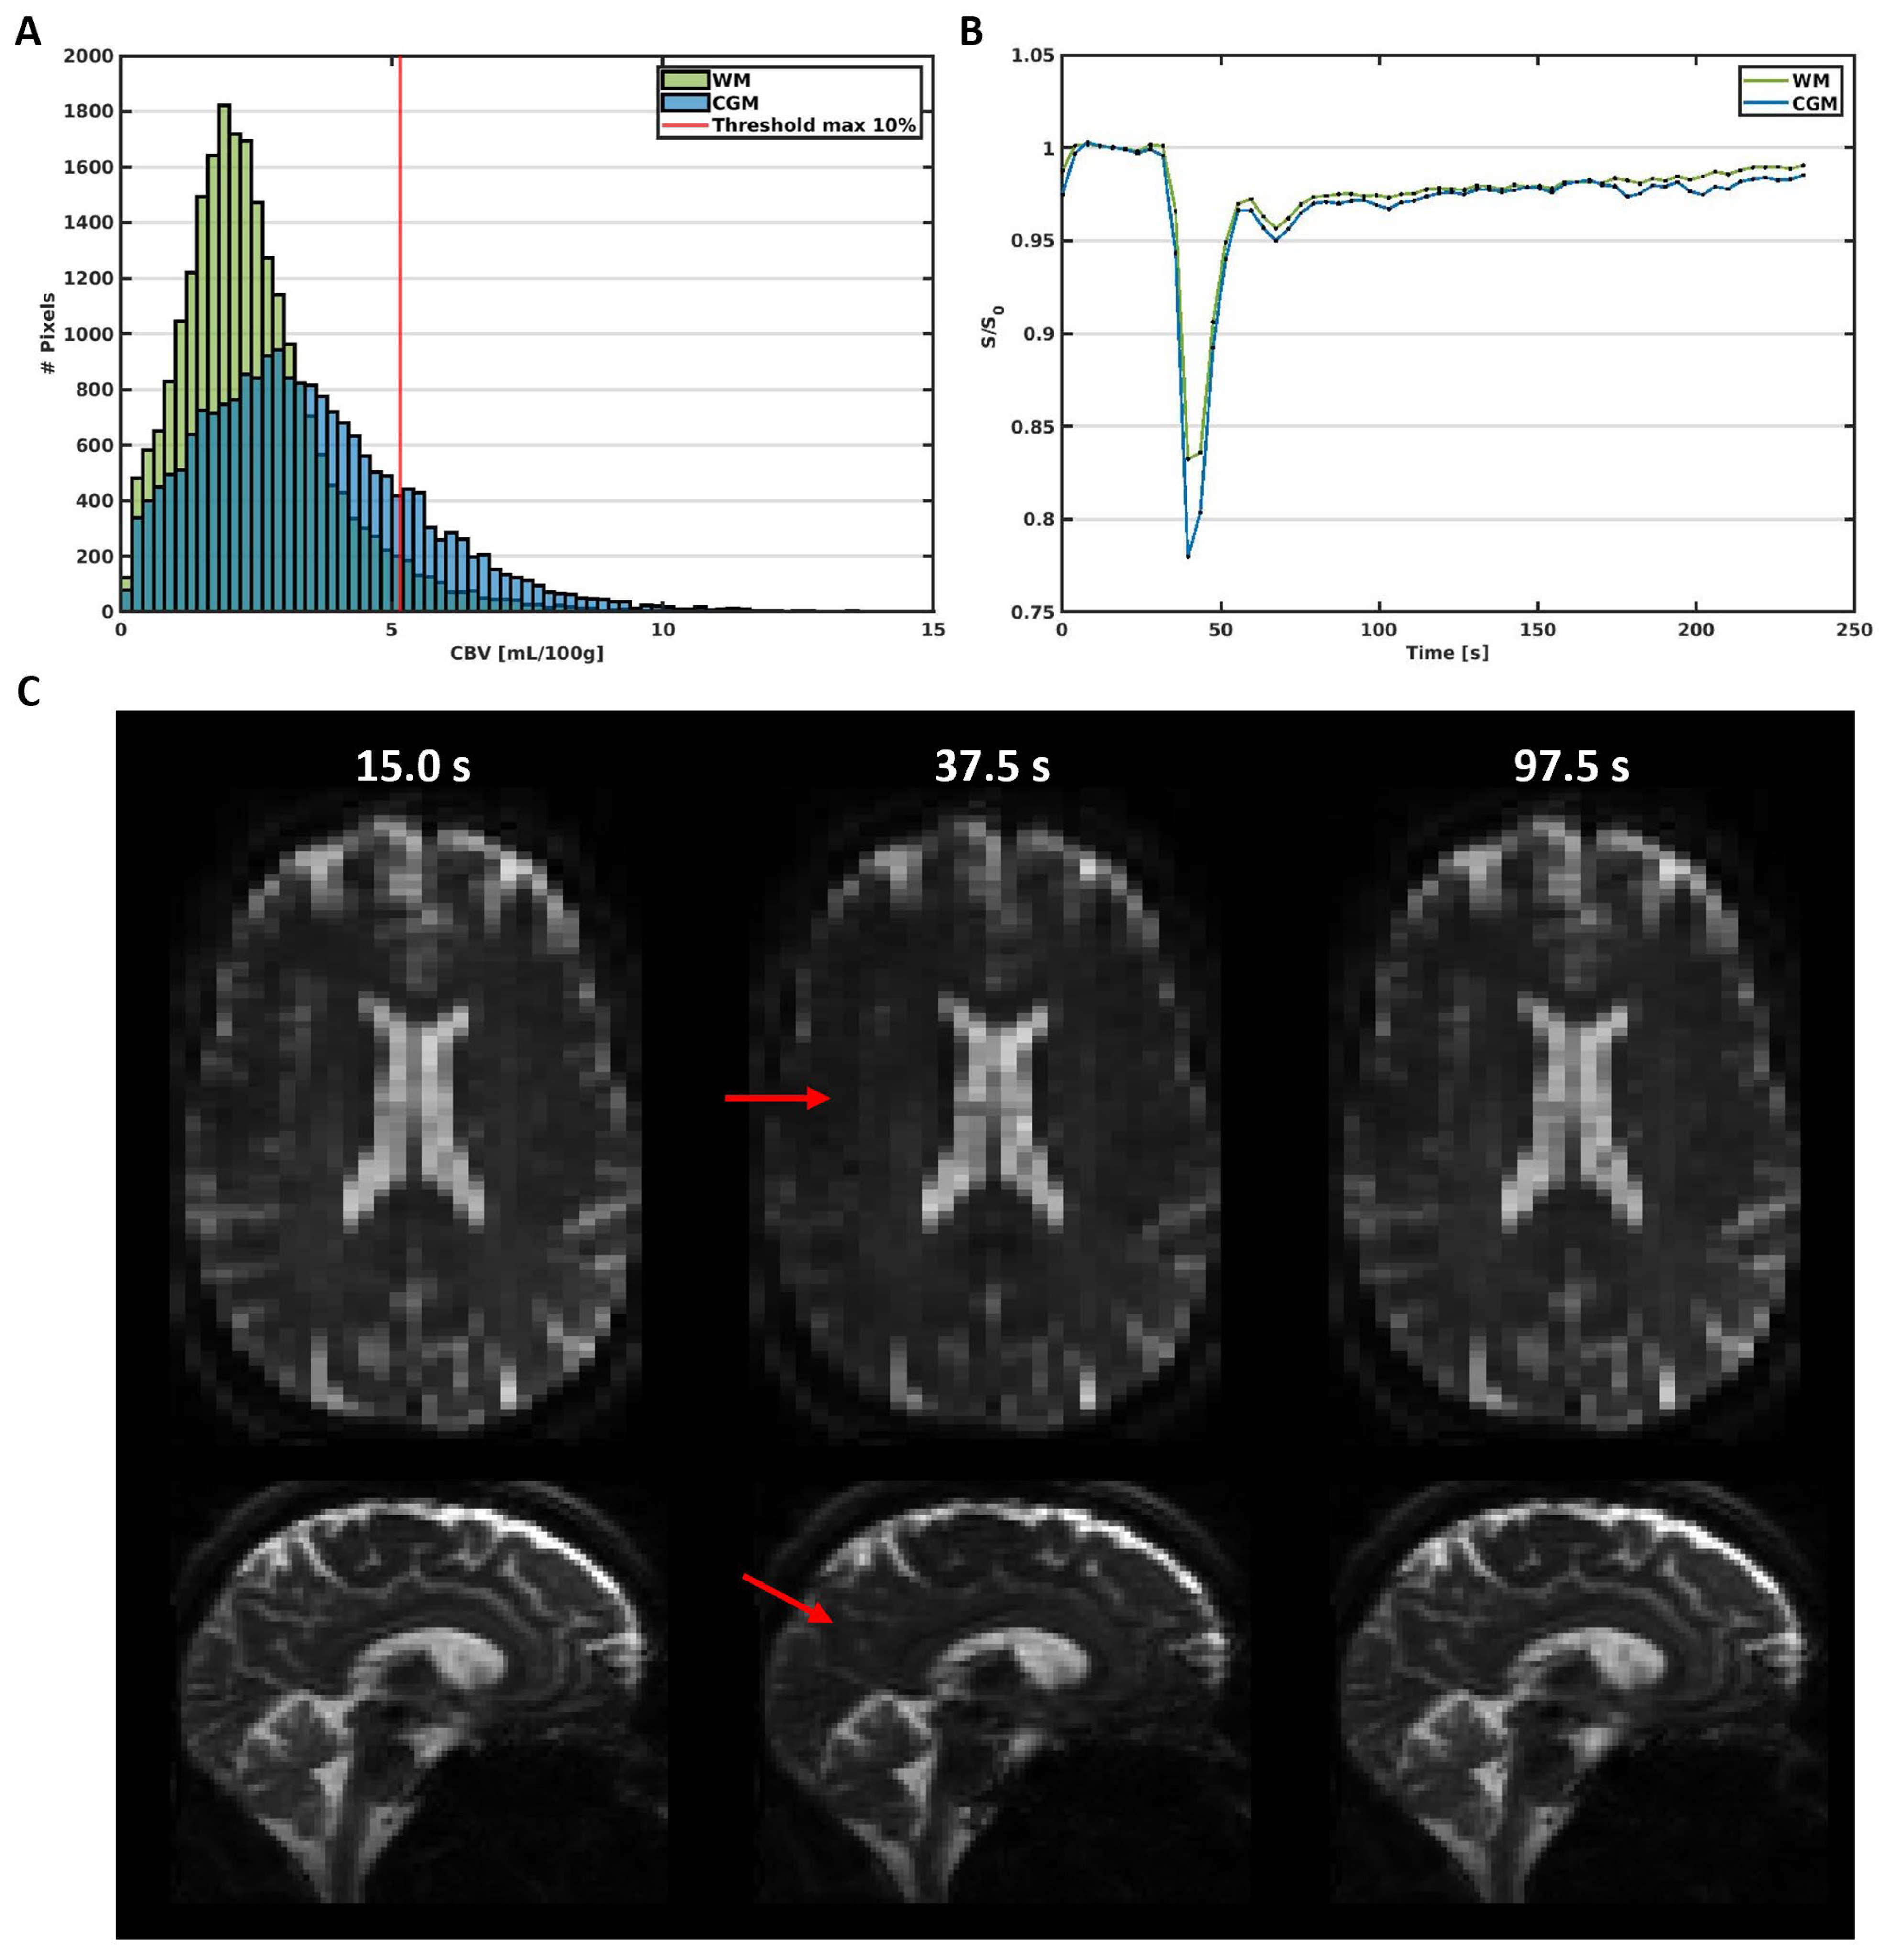

2.3.2. SE-EPI DSC-MRI